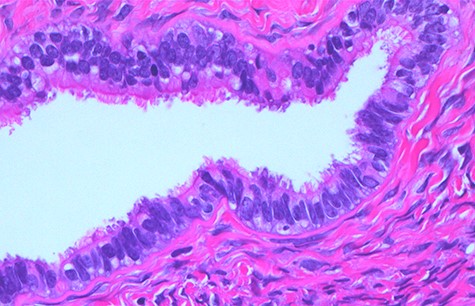

The case emphasizes the diagnostic importance of histopathology, particularly in the setting of unanticipated and sinister macroscopic findings. The macroscopic appearances of the ovaries suggested malignancy diagnosis; however, the histopathology identified benign epithelial cysts [15]. The cyst lining was comprised of a single layer of epithelial cells amid normal ovarian stroma (Figs 6 and 7). The cysts contained normal serous epithelium with cilia lining the cyst lumen. These histological findings are consistent with the Müllerian phenotype and are therefore endosalpingiosis, ectopic tubal cell deposits on the surface of the ovaries, not that of hydrosalpinges or malignant ovarian cysts as the diagnostic rollercoaster suggested [15].

Normal serous epithelium with prominent delicate cilia lining the cyst lumen; haematoxylin and eosin stain, high magnification, scale ×40.